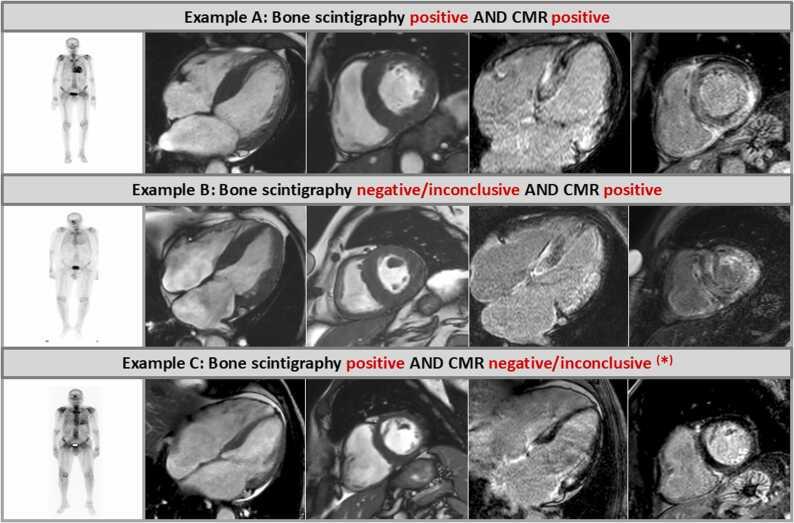

This was a real-world retrospective single-center study based on a local clinical care pipeline and we carefully analyzed clinical, laboratory, CMR, and bone scintigraphy data (and if necessary additional endomyocardial biopsy [EMB] data) in patients with suspected CA. As a major inclusion criterion, we only looked at those patients who underwent both a CMR study and a bone scintigraphy-with a clear-cut imaging finding detected by at least one imaging method.

One hundred twenty three patients in whom the final diagnosis was obtained either non-invasively based on combined findings from bone scintigraphy and monoclonal protein studies or invasively based on additional EMB findings were included. A positive CMR result indicating the presence of CA was found in 121 patients-suggesting a CMR sensitivity of 98.4% for the diagnosis of any CA. Bone scintigraphy identified 18 patients with low to moderate uptake (Perugini score = 0-1) and 105 patients with high uptake (Perugini score ≥2)-resulting in a sensitivity for bone scintigraphy of 85.4% for the diagnosis of any CA. There was an agreement ("diagnostic match") between CMR and bone scintigraphy results in 103 patients (84%) of the total study cohort, while a discrepancy ("diagnostic mismatch") was observed in 20 patients (16%). In 18 out of these 20 diagnostic mismatch cases, CMR correctly diagnosed the presence of CA despite a negative or inconclusive result on bone scintigraphy (8 with AL-CM, 8 with ATTR-CM, and 2 with EMB-proven but unspecified CA).

CMR shows a substantially higher diagnostic yield for the diagnosis of CA compared to bone scintigraphy, if a real-world cohort of patients comprising different subtypes of CA is looked at, since CMR does not only detect ATTR-CM but also depicts other CA subtypes such as AL. In case of a clear-cut positive CMR result unequivocally indicative of CA, there is no incremental diagnostic value of an additionally performed bone scintigraphy.